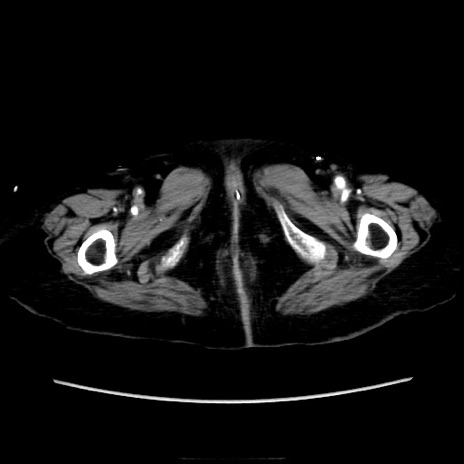

症例40(横断像)

横断像